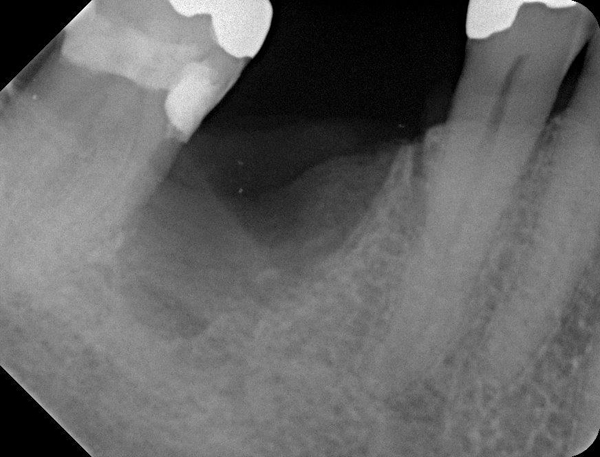

Fig 20. (Case 4) Radiograph of tooth No. 30, which had a hopeless prognosis.

Figure 20

Fig 21. Radiograph of extraction socket. Buccal plate was two-thirds resorbed.

Figure 21